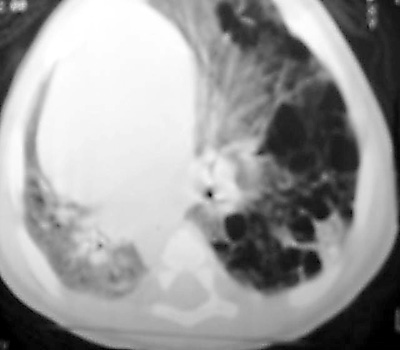

Chest CT on the same patient confirms a Type I CCAM with a large dominant cyst

surrounded by multiple smaller cysts